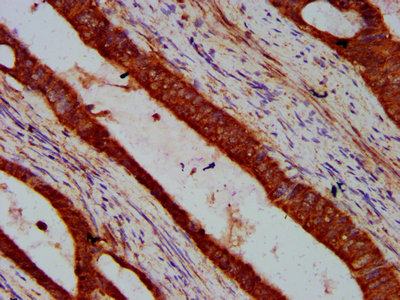

IHC image of CSB-PA768235LA01HU diluted at 1:600 and staining in paraffin-embedded human colon cancer performed on a Leica BondTM system. After dewaxing and hydration, antigen retrieval was mediated by high pressure in a citrate buffer (pH 6.0). Section was blocked with 10% normal goat serum 30min at RT. Then primary antibody (1% BSA) was incubated at 4°C overnight. The primary is detected by a biotinylated secondary antibody and visualized using an HRP conjugated SP system.